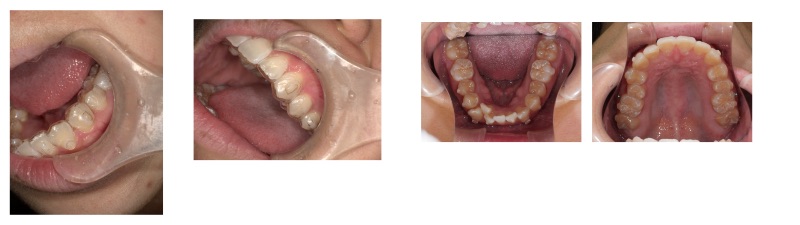

Hさん当院スタッフの症例です

アンフィットのための追加アライナーのについての質問です

治療計画通りに進んでなくて困っています問題なく交換できていたと思っていたのですが、

33枚目(ステージングでは下顎5番の遠心移動が終了するところ)で見たら

アライナーはパカパカ浮いていることはないですが

下顎5番に付いているアタッチメントの位置にアライナーがはまってなかったのを発見しました

よく見ると上顎もアライナーがアタッチメントにはまってないところがありました

もうダメだと思い、スキャンをして提出しました

返ってきたアニメーションは、62枚(1回目も64枚でした)で、また下顎の7番の遠心移動からの計画になっていました

これって全然動いていないということでしょうか?

途中経過は下顎遠心移動に伴い、歯間部に空隙ができていたんです

私のイメージでは、下顎は7、6、5の遠心移動が終わったのだから追加アライナーは

4番を動かすところから始まるんだと思っていました。

アンフィットからの立て直しが初めてなのですが、どういうことが起きているのか解説して頂きたいです

自分では67の遠心移動は終了したとしてスマーティーチェックを作ってみました

どうぞよろしくお願いします

現在の口腔内写真を添付します -